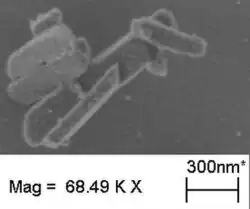

The malaria parasite, therefore, detoxifies the hematin, which it does by biocrystallization—converting it into insoluble and chemically inert β-hematin crystals (called hemozoin).[13][14][15] In Plasmodium the food vacuole fills with hemozoin crystals, which are about 100–200 nanometres long and each contain about 80,000 heme molecules.[4] Detoxification through biocrystallization is distinct from the detoxification process in mammals, where an enzyme called heme oxygenase instead breaks excess heme into biliverdin, iron, and carbon monoxide.[16]

Several mechanisms have been proposed for the production of hemozoin in Plasmodium, and the area is highly controversial, with membrane lipids,[17][18] histidine-rich proteins,[19] or even a combination of the two,[20] being proposed to catalyse the formation of hemozoin. Other authors have described a heme detoxification protein, which is claimed to be more potent than either lipids or histidine-rich proteins.[12] It is possible that many processes contribute to the formation of hemozoin.[21] The formation of hemozoin in other blood-feeding organisms is not as well-studied as in Plasmodium.[22] However, studies on Schistosoma mansoni have revealed that this parasitic worm produces large amounts of hemozoin during its growth in the human bloodstream. Although the shapes of the crystals are different from those produced by malaria parasites,[23] chemical analysis of the pigment showed that it is made of hemozoin.[24][25] In a similar manner, the crystals formed in the gut of the kissing bug Rhodnius prolixus during digestion of the blood meal also have a unique shape, but are composed of hemozoin.[26] Hz formation in R. prolixus midgut occurs at physiologically relevant physico-chemical conditions and lipids play an important role in heme biocrystallization. Autocatalytic heme crystallization to Hz is revealed to be an inefficient process and this conversion is further reduced as the Hz concentration increases.[27]